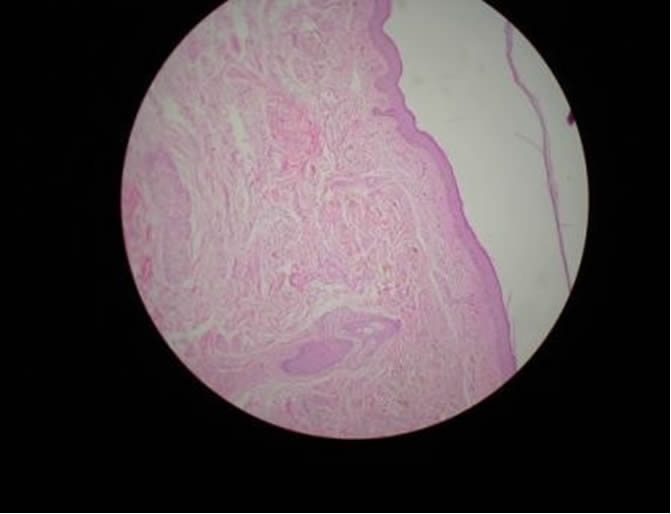

OCRONOSIS - HISTOPATOLOGIA - DR. PIQUERO